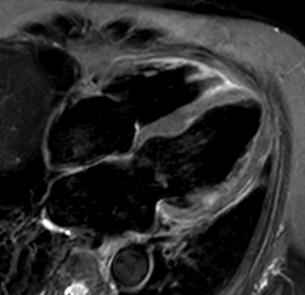

心筋遅延造影MRI検査

心筋遅延造影MRI検査はガドリニウム造影剤を用いることで、心臓の筋肉の様子を詳細に観察することが可能です。心筋梗塞や心筋症などで心筋が傷害を受けると、その部位の心筋細胞が壊れて、ガドリニウム造影剤が通常は染み込んで行かないはずの心筋に染み込んで行きます。その造影心筋の進達度により、心筋の組織性状や心筋の生存性(バイアビリティ)の指標としても利用され、現在原因不明の心不全症例の精査や心筋梗塞後の評価に用います。